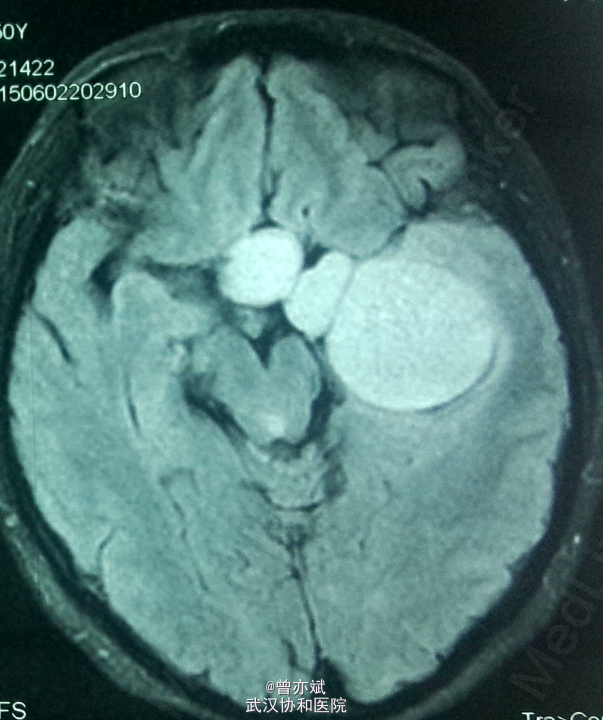

查体:左眼视力0.8 颞侧偏盲,右眼视力 0.5 余无明显阳性体征。既往无特殊。 MRI: 稍长 T1,高flair信号,增强明显强化 ,其内点片状强化减低区。诊断:鞍区、中颅窝底巨大占位,考虑脑膜瘤可能性大。

诊断:脑膜瘤?海绵状血管瘤? 处理:手术切除 。

从 MRI上看,矢状位 增强可疑脑膜尾征,增强虽然明显但 不均匀 ,酷似脑膜瘤表现,手术中所见血供丰富,肿瘤实质多为血窦,考虑海绵状血管瘤。如果术前 能 诊断是海绵状血管瘤 ,是开颅手术还是分次伽马刀? 有大神指点一二不?